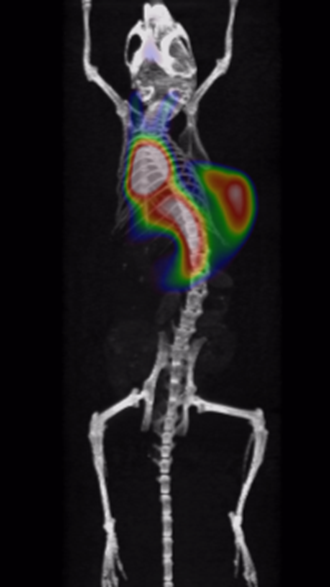

It has been proved that Cu-64-marked nanoantibodies are well-targeting for tumors, with high local uptake and long retention